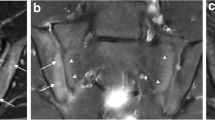

In addition to the features that were scored semi-quantitatively and quantitatively, some obvious other incidental findings were depicted on CT as well as on sCT, such as spina bifida occulta (2 cases), ossification centers of the apophysis of the iliac crest (4 cases) and an enostoma (1 case) (Fig. 1).

Some incidental findings were seen on both MRI-based synthetic CT (sCT) (left images a, c, and e) and CT (right images b, d, and f). a–b Spina bifida occulta of S1 (arrowhead) in a 15-year-old girl in an axial plane. Also note the ossification centers of the apophysis of the iliac crest that can be seen as well (arrows). c–d Lumbosacral transitional anomaly without bony fusion on the left side (asterisk) in a 12-year-old boy in a paracoronal plane. Also note the white line in the right SI joint (black arrowhead), consistent with an artifact on sCT (this was not seen on CT). e–f Enostoma in a 16-year-old female on the left side of S1 in a paracoronal plane (black arrows)

Ankylosis and bony bridges of the SI joint are known structural lesions in sacroiliitis [3, 4, 10], however they were not expected in this normal population. In our study, bony bridges were scored in only 1 patient on sCT on the left side, not on CT, resulting in a kappa value of 0 (Table 3) (Table S1). Bony bridge-like features are a known artifact on sCT and a potential pitfall that has already been described in adults when using sCT for the diagnosis of sacroiliitis. Morbée et al. have shown that the vacuum phenomenon can be falsely seen as the bony bridge on sCT in SI joints [21]. In our case too, this rather thin white “artifactual” line crossing the SI joint on sCT (Fig. 1b.) did not mimic true ankylosis as can be seen in sacroiliitis, also no other features of sacroiliitis were present. In our normal study group, we also detected an incidental enostoma (Fig. 1e–f.) near the SI joint, which was equally seen on CT and sCT. This is promising as sCT might be used as well for assessing sclerosis as a structural lesion of sacroiliitis [21].